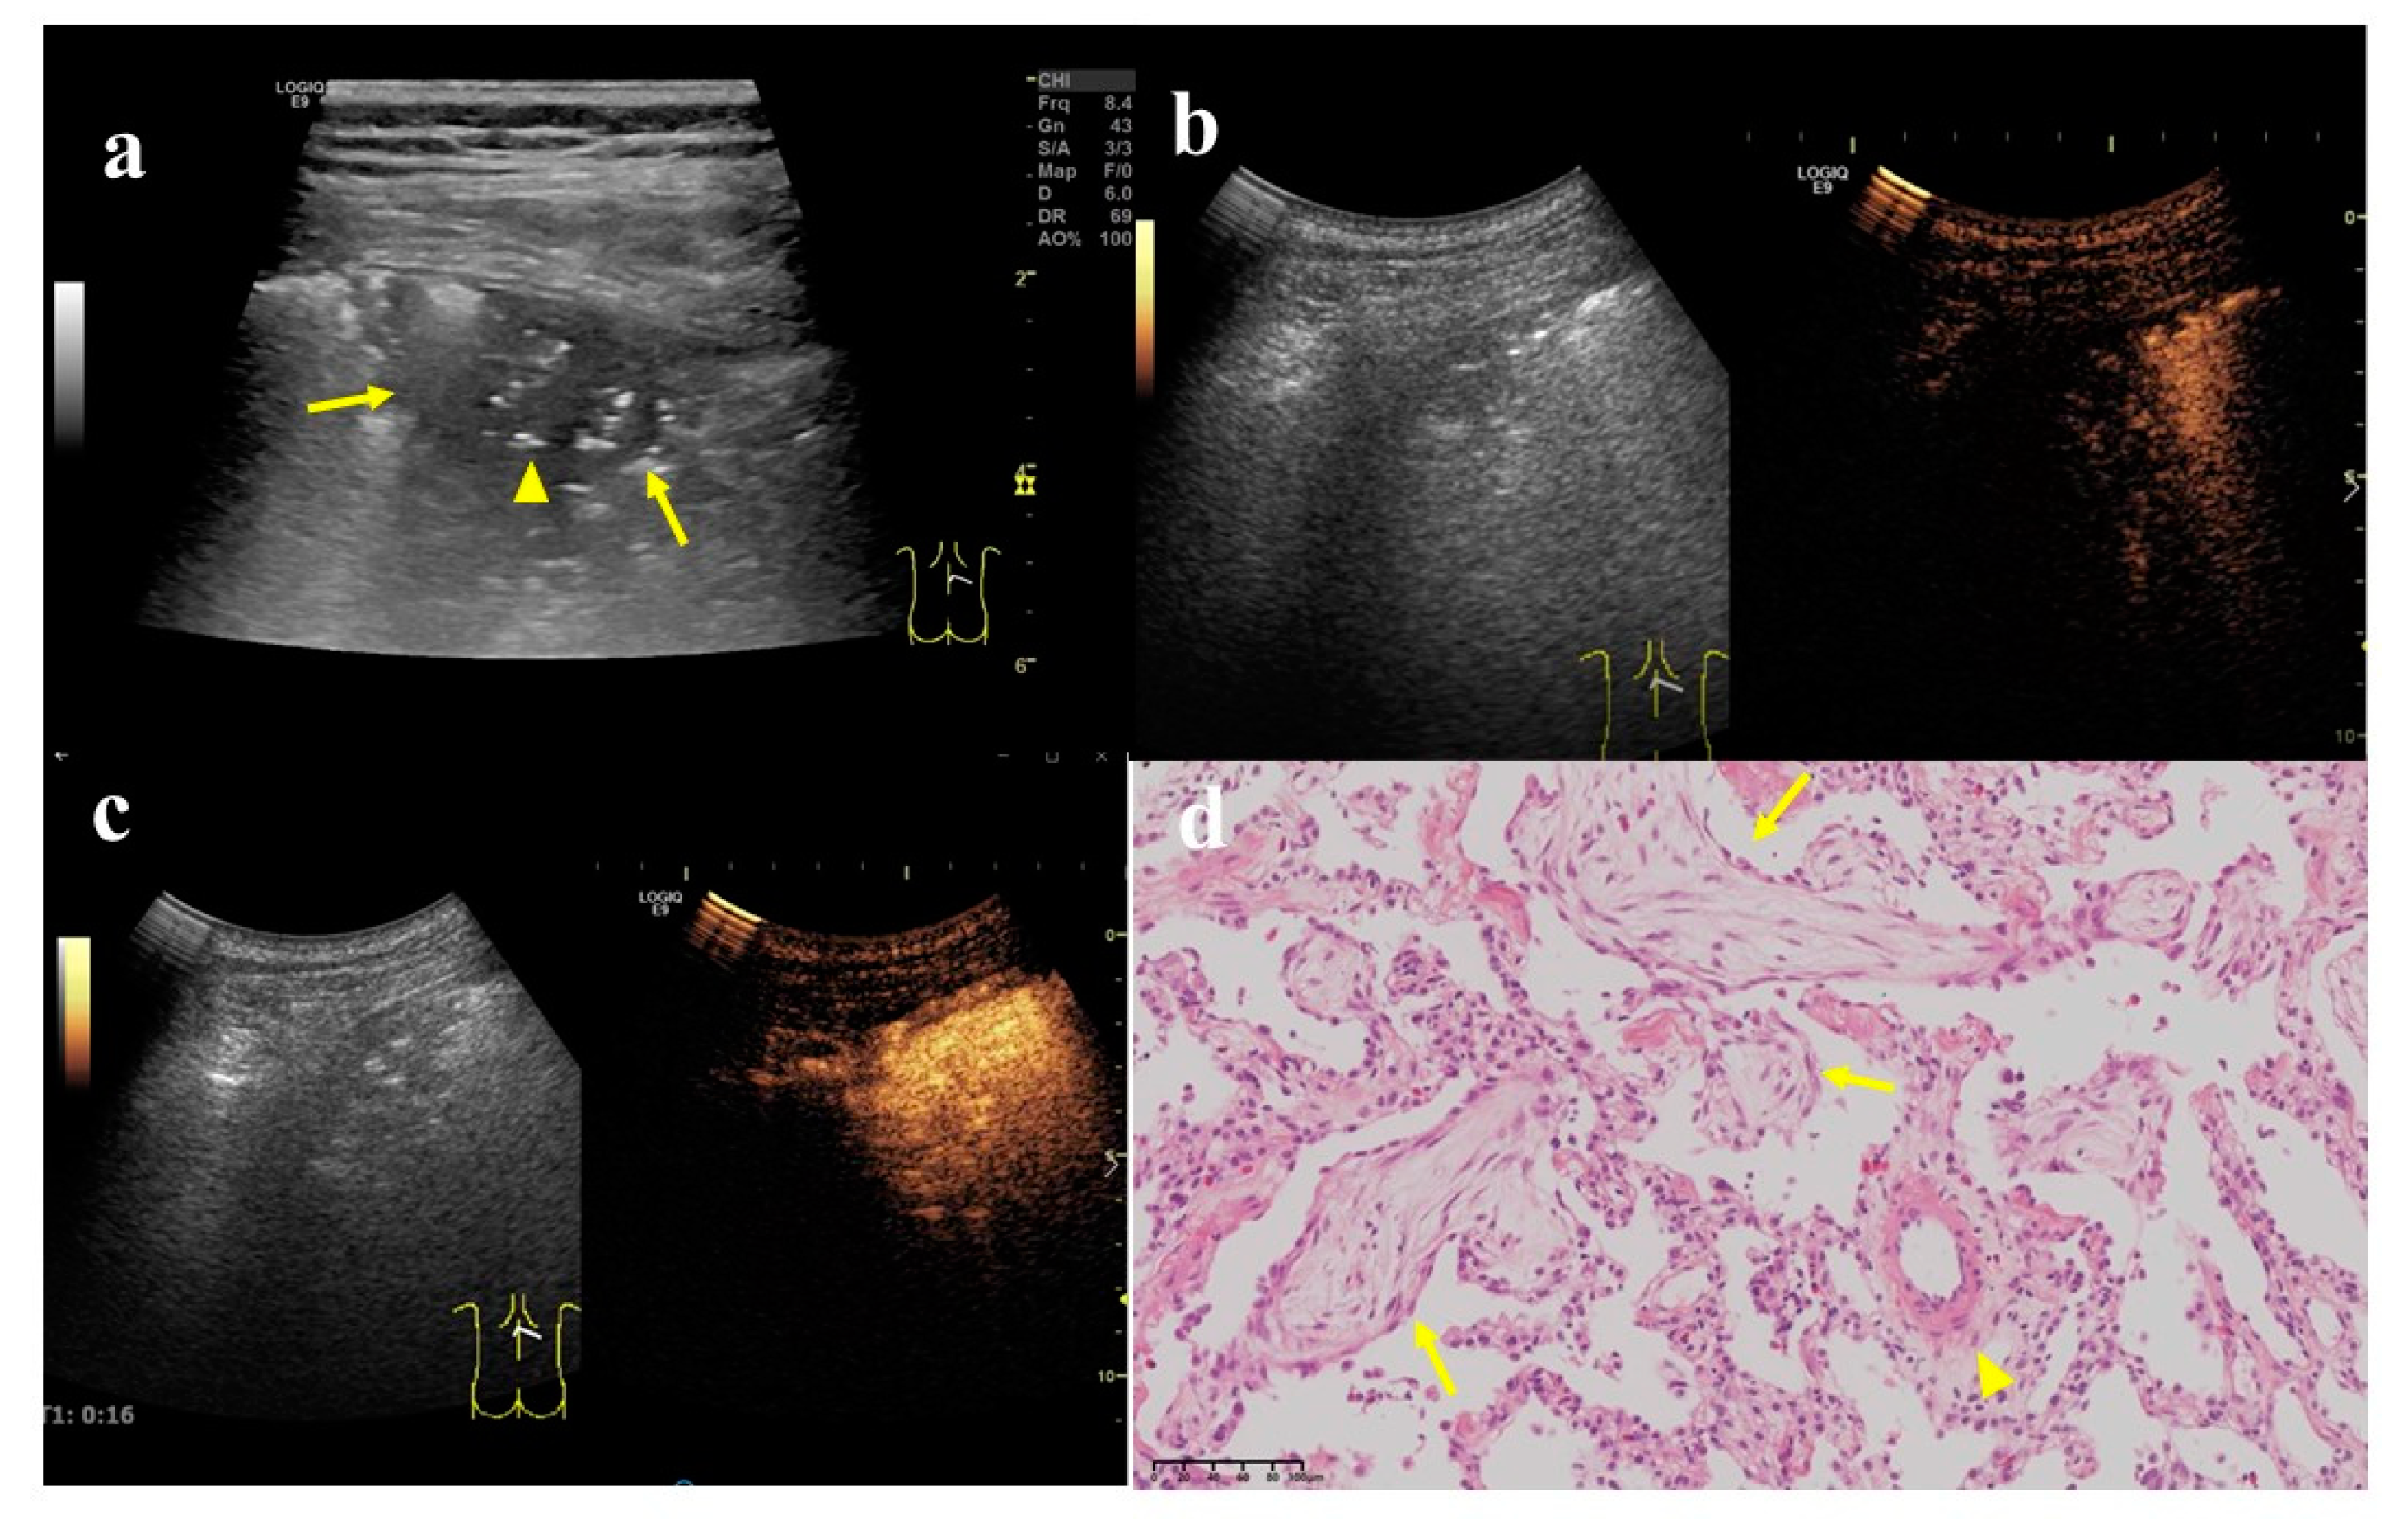

Figure 4.

A 62-year-old female, who underwent total gastrectomy for gastric cancer 6 years ago and breast-conserving surgery for breast cancer 2 years ago, was coughing and expectorating for one month. (a) A wedge-shaped hypoechoic lesion (arrow) can be seen on the ultrasonic image of the right lung, with air bronchial sign inside (arrow head). Either angle between lesion border and thoracic wall was an acute angle. (b) After injection of contrast agent, the lesion began to enhance in 7 s, which was a uniform hyper-enhancement. The lung tissue began to enhance in 9 s, later than the lesion. (c) The enhancement of the lesion reached the peak in 16 s, and was a uniform enhancement. (d) An ultrasound-guided biopsy was performed. The pathological examination showed alveolar structure existed, the spacing was widened, and scattered lymphomonocytes could be seen in the focal alveolar cavity with cellulose exudation. Masson bodies (arrow) and small branch of pulmonary artery (arrow head) can be seen inside (×200). These findings conformed to the changes in organized pneumonia. After treatment with Medrol 8 mgqd for two months, the lesion became smaller and did not enlarge at the time of writing.